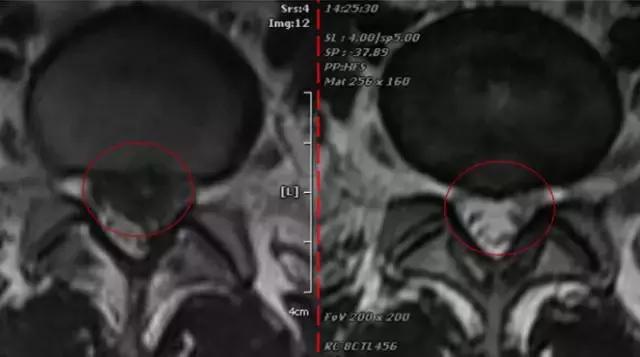

手术前 手术后